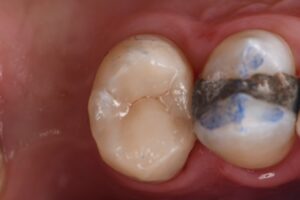

Extreme DME case using the Rhondium DME wedge in sequence with the Garrison Compositight system with a supercomposite placed incrementally to support what little is left of this extremely-compromised second bicuspid.

#VocoGrandioSO #RhondiumDME #GarrisonCompositight